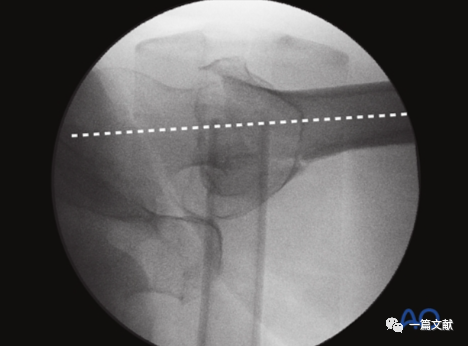

体位如下图,C臂机从水平位适度旋转,使透视射线与冠状面夹角约15°。

透视射线与患肢长轴夹角约30°-45°,如下图: